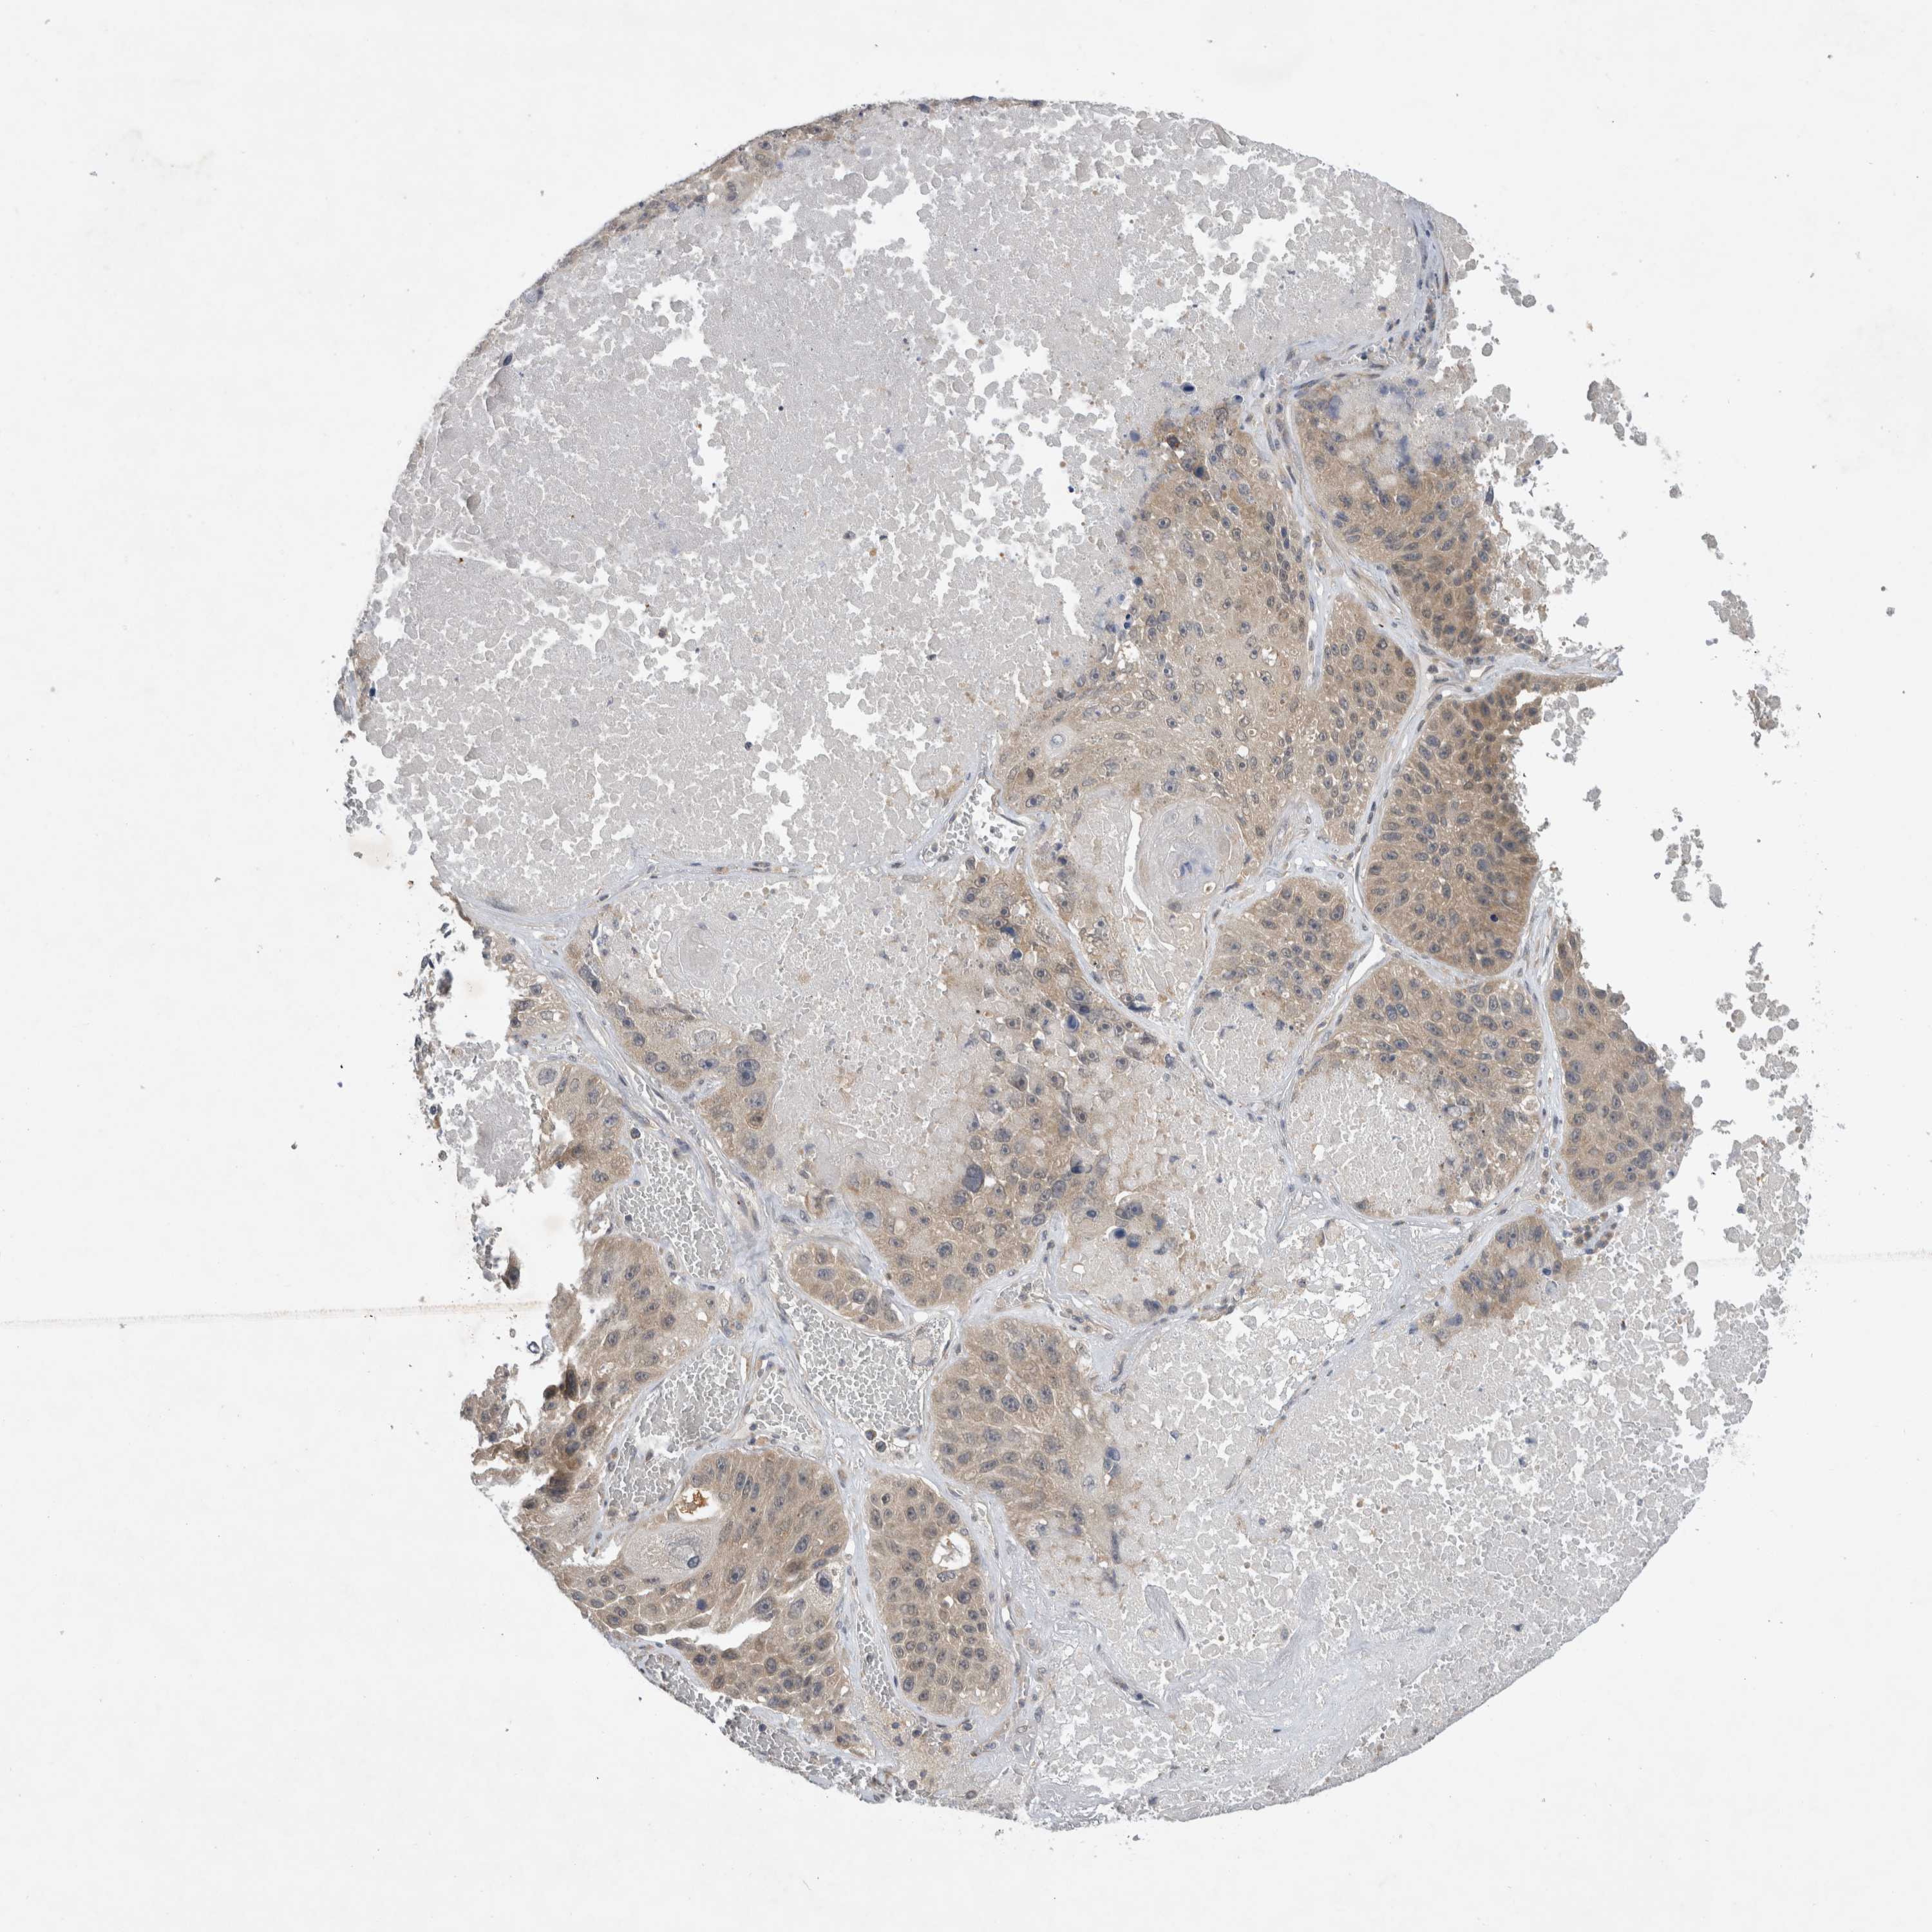

CANCER LUNG CANCER Show tissue menu

LUAD TCGA LUAD VALIDATION LUSC TCGA LUSC VALIDATION PROTEIN LUAD CPTAC PROTEIN LUSC CPTAC PROTEIN EXPRESSION